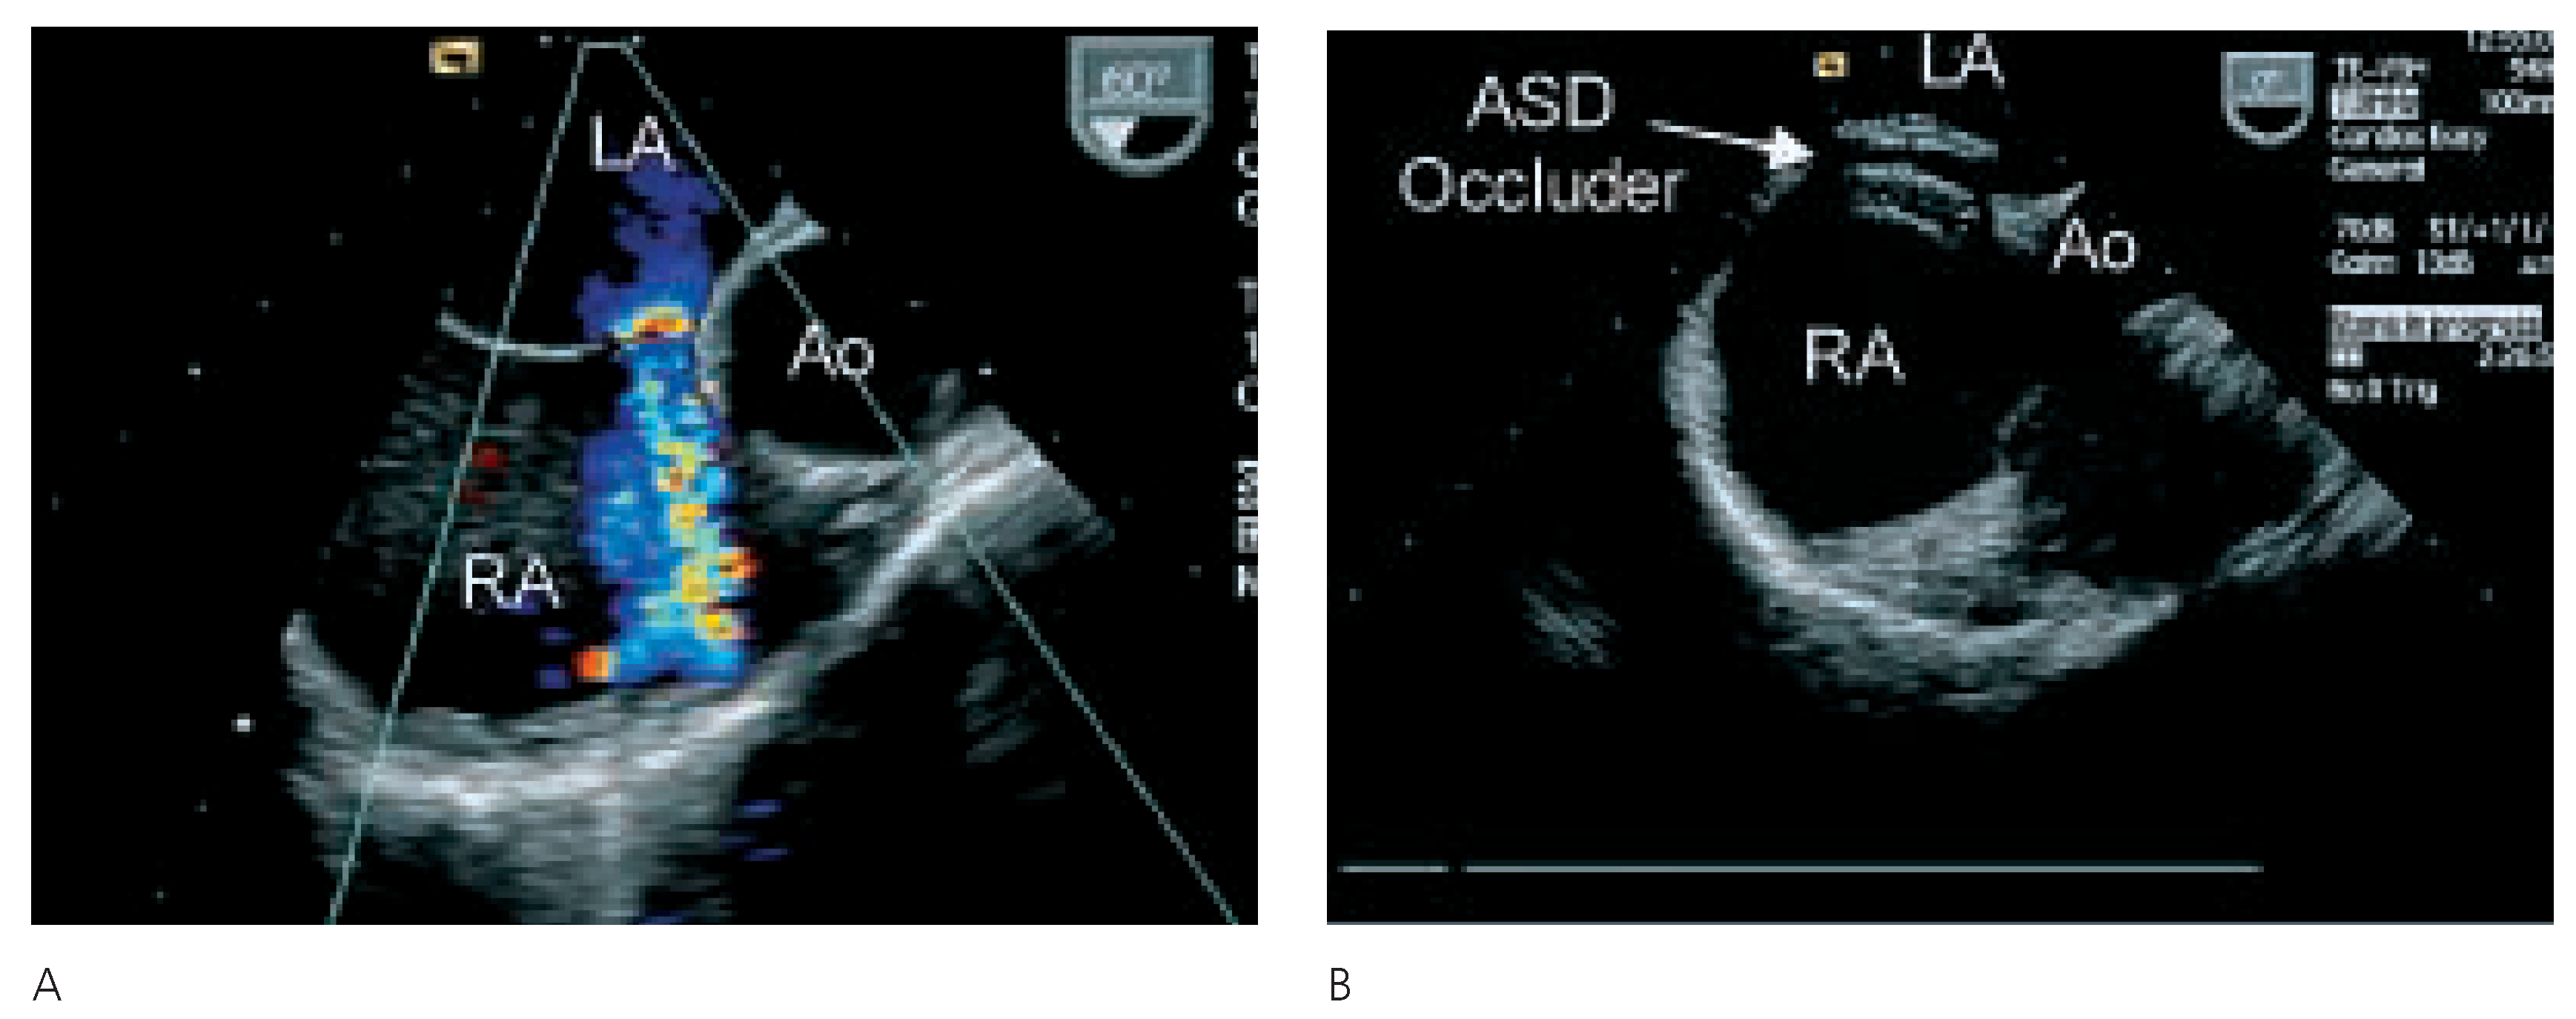

Nach eingehender Diskussion der Befunde mit allen involvierten Kollegen, der Patientin und ihren Angehörigen wurde die Patientin zum perkutanen Verschluss des ASD an die Kardiologie des UniversitätsSpitals Zürich überwiesen. In der invasiven Herzkatheteruntersuchung konnte eine koronare Herzkrankheit und eine pulmonal-arterielle Hypertonie ausgeschlossen werden. Der mittlere pulmonal-arterielle Druck betrug 19 mm Hg und der pulmonale Widerstand 81 dyn×sec×cm–5. Vor Verschluss des Vorhofseptumdefektes, welcher in Narkose und unter transösophagealer Überwachung durchgeführt wurde, konnte oxymetrisch kein Rechts-Links-Shunt nachgewiesen werden. Der Links-Rechts-Shunt betrug unter diesen Bedingungen zudem auch nur 14%. Nach Sondieren des Vorhofseptumdefektes wurde mittels Messballon eine ASD-Grösse von 19 mm gemessen. Es wurde ein Amplatzer-ASD-Occluder® 20 mm im Vorhofseptum plaziert. Aufgrund der Lokalisation des ASD mit praktisch fehlendem Saum gegen die Aorta kam der Schirm nahe der Aortenwurzel zu liegen (Figure 3 and Figure 4). Die orale Antikoagulation wurde in der Folge abgesetzt und als Nachbehandlung erhielt die Patientin 100 mg Aspirin® und 75 mg Plavix® für drei Monate, gefolgt von Aspirin® 100 mg für weitere drei Monate. Ebenfalls wurde für sechs Monate eine Endokarditisprophylaxe durchgeführt. Nach dem Eingriff war die Anstrengungsdyspnoe praktisch behoben und die transkutane Sauerstoffsättigung betrug nun im Stehen und unter Belastung immer über 90%. In der transthorakalen Echokardiographie sechs Monate nach dem Eingriff konnte kein Shunt auf Vorhofebene mehr nachgewiesen werden. Der Amplatzer-Occluder lag in regelrechter Position. Weiterhin war der systolische pulmonal-arterielle Druck nicht erhöht.

Figure 4.

A Ausmessen der ASDGrösse mittels Ballon. B Kontrolle der AmplatzerOccluder-Lage mittels TEE. C Amplatzer-Occluder in Position.

Die Therapie des Platypnoe-Orthodeoxie-Syndroms ist die Ausschaltung des Shunts. Bei intrakardialen Shunts ist die Therapie der Wahl bei geeigneten anatomischen Verhältnissen heute ein kathetertechnischer Verschluss des PFO oder ASD (Figure 3 and Figure 4). Der perkutane Verschluss des PFO ist wegen der sehr hohen Erfolgsrate und den niedrigen Komplikationen die Methode der Wahl beim Vorliegen eines PFO [18]. Beim ASD hat sich der perkutane Verschluss ebenfalls als bevorzugte Therapie gegenüber dem chirurgischen Verschluss etabliert. Die Erfolgsrate des perkutanen ASD-Verschlusses liegt bei 96%. Die Komplikationsrate (z.B. Blutungen an der Einstichstelle, Arrhythmien, Schirm-Embolisationen) ist mit 7% sehr niedrig [12]. Chirurgisch gelingt der ASD-Verschluss immer, es muss jedoch mit einer viel höheren Komplikationsrate (24%) gerechnet werden [12]. Der Langzeiterfolg ist bei beiden Techniken identisch [12].